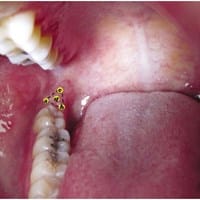

Me duele y tengo hinchada la zona de atrás de las muelas ¿Puede ser cáncer?

respondió: I. Hola. En mi caso no tengo conocimientos sobre odontología, pero quería comentar que tambien he tenido molestias e hinchazón en la que creo en esa misma zona, trígono retromolar, y luego desaparecieron sin más. Pensé que se trataba del nacimiento...